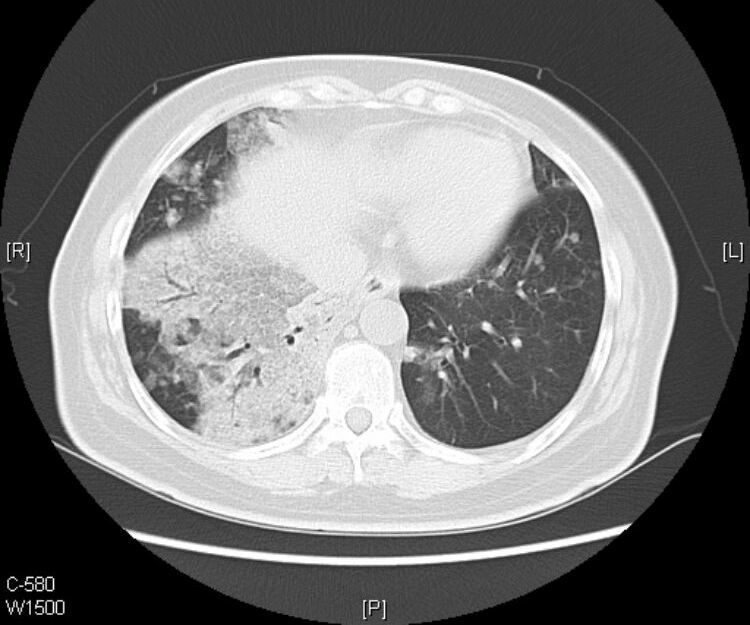

接着看她往下的CT层面:

从CT片上我们可以看到:老人的黏液腺癌还发生了气道转移。

什么是气道转移:

定义:癌细胞从原发灶通过气道非连续性传播到邻近或远端肺实质。

CT提示气道播散的征象包括:多发小叶中心结节,分支模糊呈树芽征,通常边界不清,可见磨玻璃影。

1.气道播散形成的结节呈聚集分布,可以融合增大,有时也可形成空腔。

2.当转移灶远离原发灶时,所形成结节多分布于肺叶下部。

3.在患有肺腺癌的患者CT中发现持续存在或逐渐增长的小叶中心结节时,应考虑到气道转移的可能性,尤其是这些结节伴有侵蚀性、粘液性,呈乳头状或微乳头状分型。